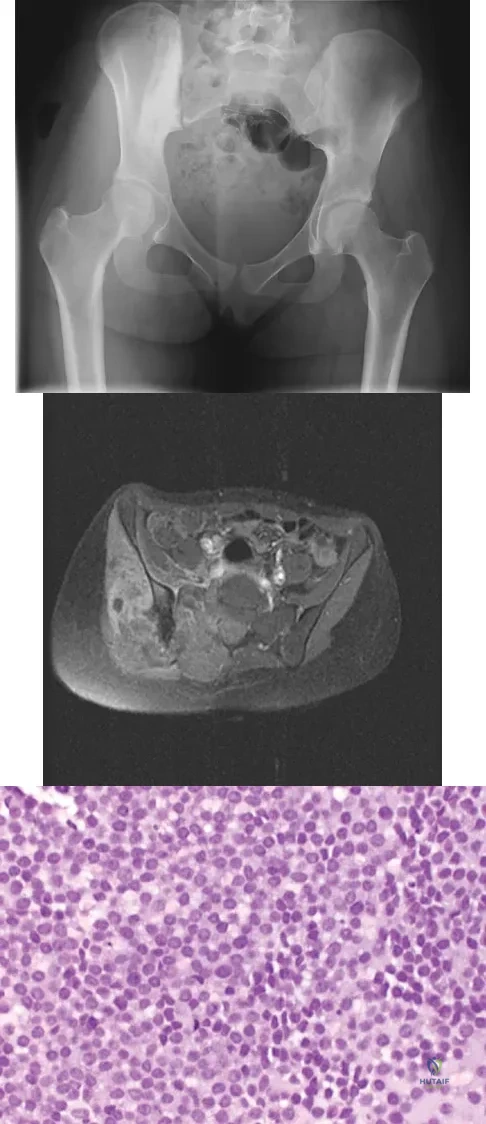

A 16-year-old girl has had hip pain for 1 year. Approximately 2 months ago she noted the development of a hard mass in the right buttock that has steadily increased in size. She now reports severe pain in the right buttock, with radiation down the leg and numbness involving the right foot and toes. A radiograph is shown in Figure 70a and an axial postcontrast T1-weighted MRI scan is shown in Figure 70b. A biopsy specimen is shown in Figure 70c. The chest CT shows multiple lung metastases. Treatment of this lesion should consist of

Explanation